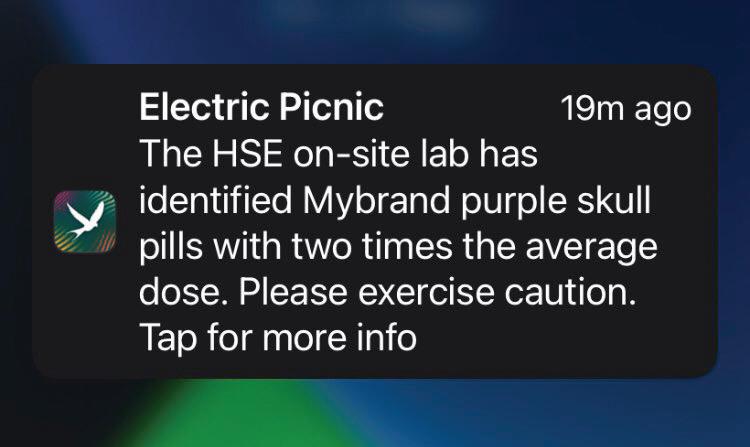

Drug checking pilot programme at EP